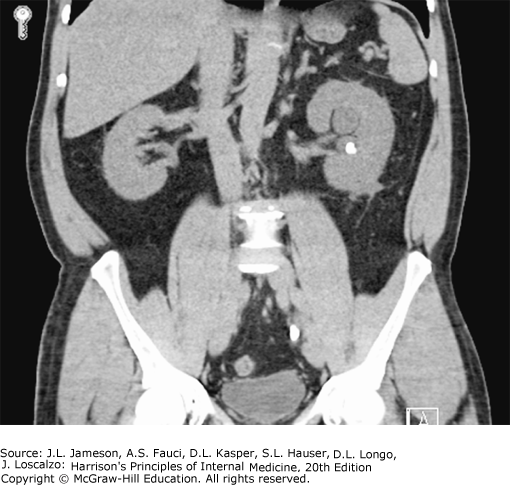

Coronal noncontrast CT image from a patient who presented with left-sided renal colic. An obstructing calculus, present in the distal left ureter at the level of S1, measures 10 mm in maximal dimension. There is severe left hydroureteronephrosis and associated left perinephric fat stranding. In addition, there is a nonobstructing 6-mm left renal calculus in the interpolar region. (Image courtesy of Dr. Stuart Silverman, Brigham and Women’s Hospital.)